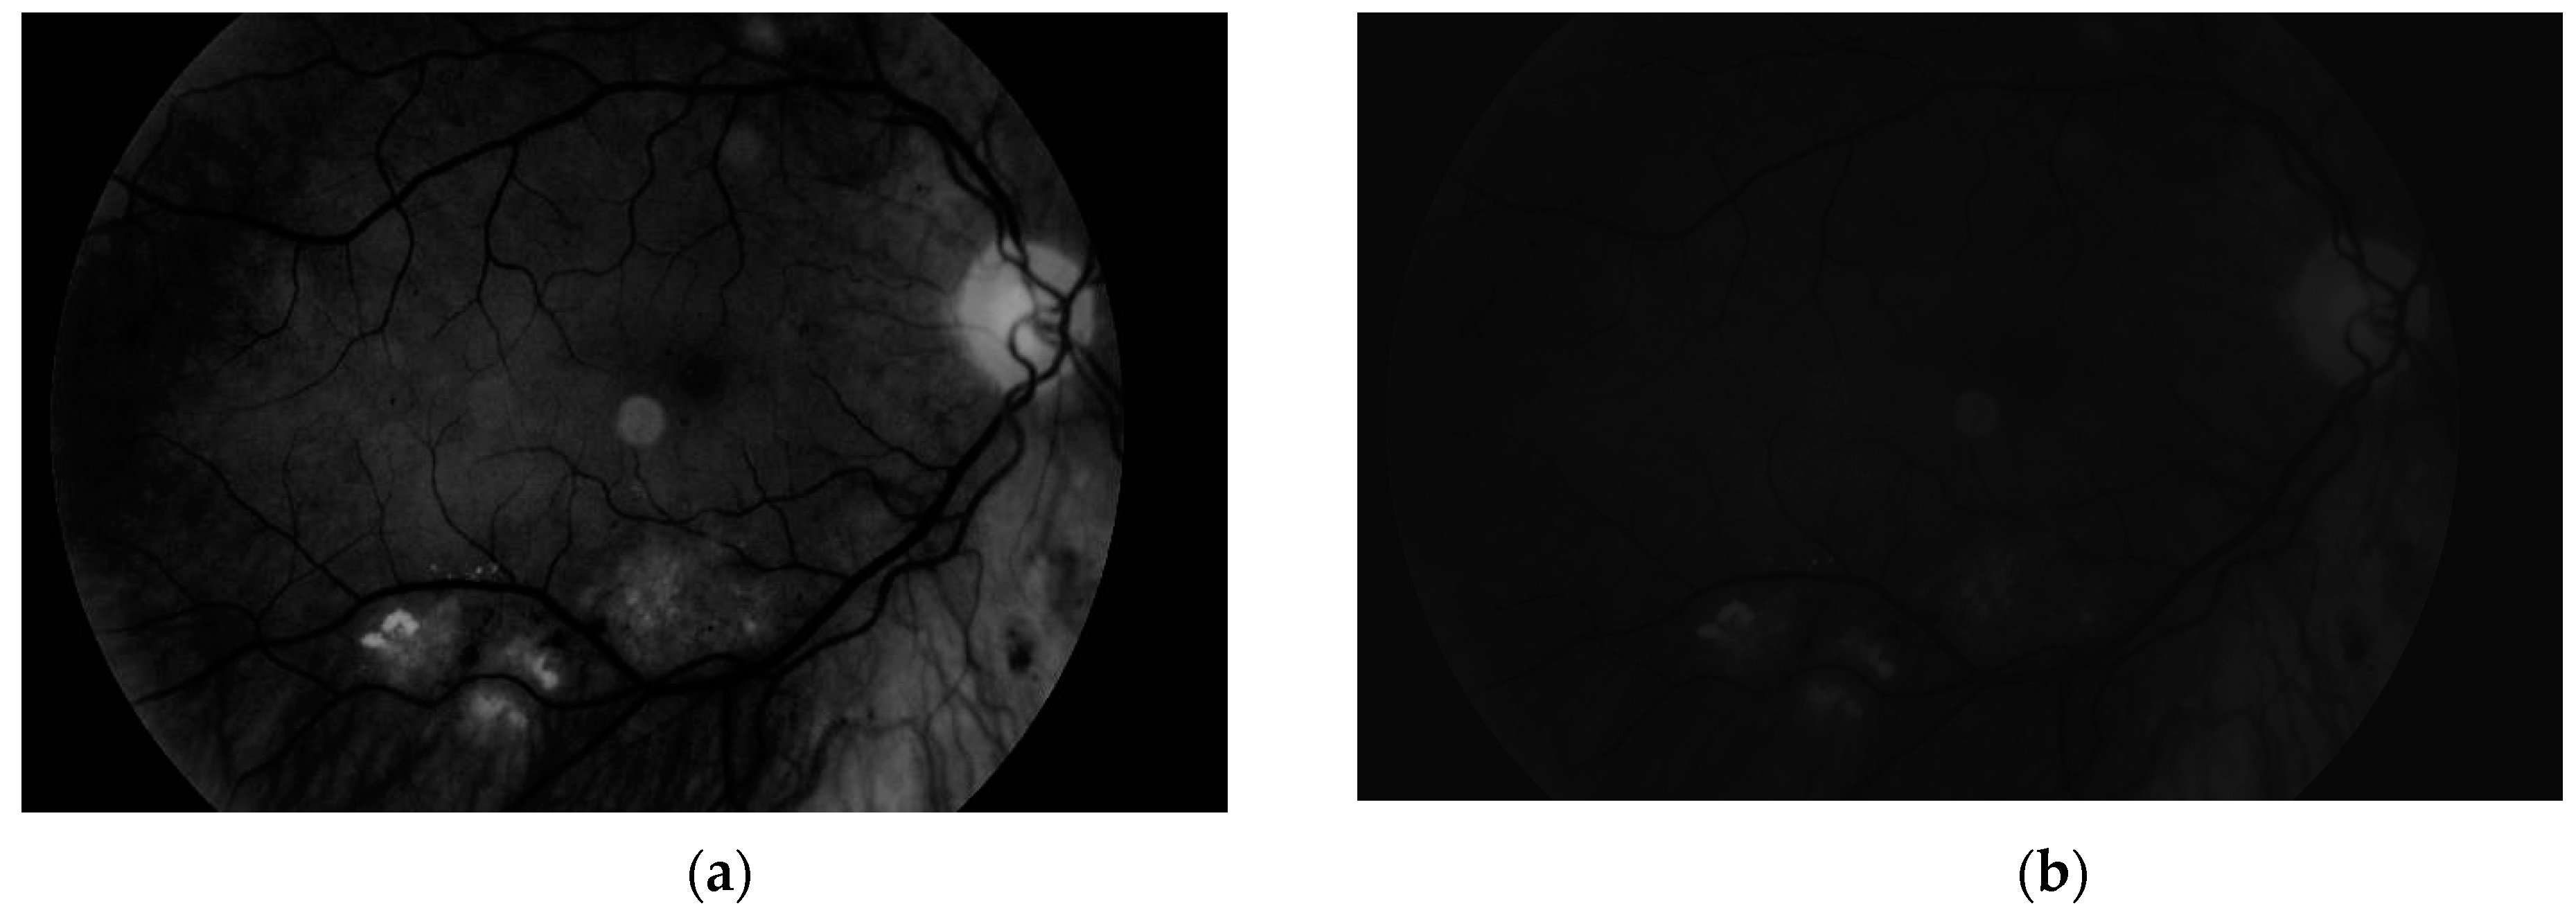

To obtain proper vascular patterns, a local entropy binarization algorithm was used to get proper white veins on a black background. However, this has caused a few small elements that do not belong to retinal veins to be shown in the image, alongside the marked veins. Additional elements are removed on the basis of their length. If they are too short (the length in pixel number is selected arbitrarily), they are deleted–we assume that these elements are not parts of real veins. The results of both of these steps are presented in Figure 13.

Via this step, the vascular pattern of the processed retina was obtained. In the form presented in Figure 13b, it will be applied to the obtained image after the preprocessing stage (Figure 8b). Both of these images are considered in the next module.

Figure 13. Image (a) after binarization and (b) after short vessel removal.

Sensors 19 00695 g013